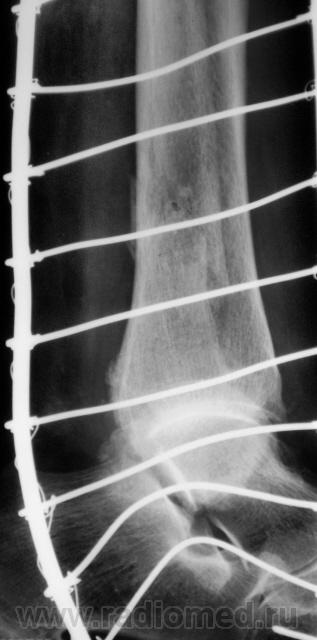

Перелом наружной и задней лодыжек. Подвывих в голеностопном суставе кнутри. Подвывих в тараннопяточном суставе. Разрыв дистального межберцового сочленения.

Переломы латеральной и медиальной лодыжек, пронационный подвывих в голеностопном суставе, латеральный подвывих в таранно-пяточном, разрыв межберцового синдесмоза.

Удивлюсь, если нет перелома таранной...

Almo правильно задал вопрос, это касается терминологии. Про вывих стопы говорят, когда имеется вывих в г/ст суставе, а подтаранный N. Если имеется вывих в голенностопе и в подтаранном в противоположные стороны, т.е. смещается только таранная кость, говорят о вывихе таранной кости. Данный случай относится именно к последнему.